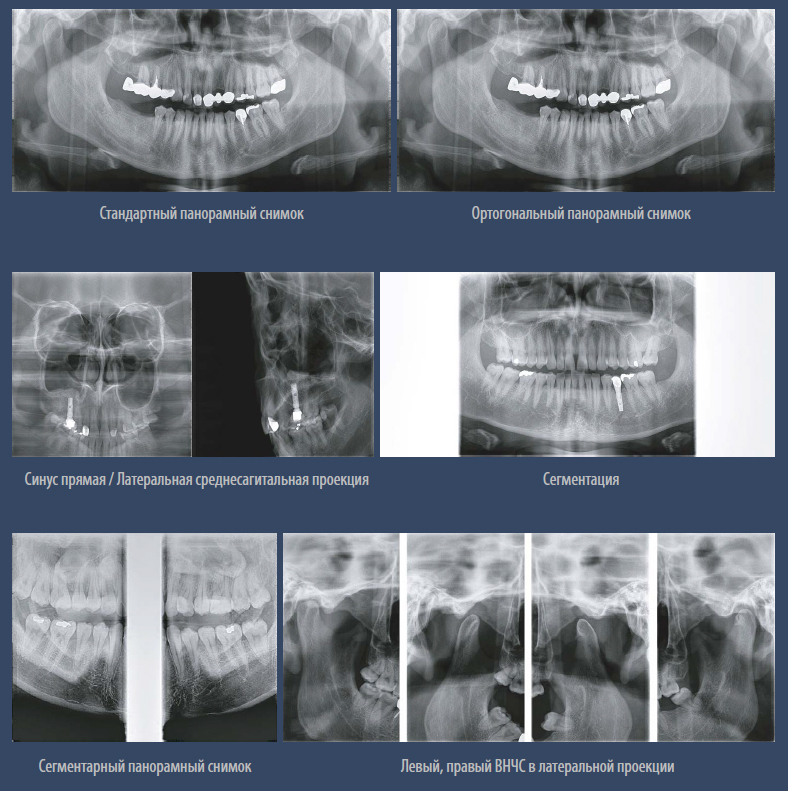

Режимы экспозиции панорамной съёмки.

– Стандартный панорамный

– Ортогональный панорамный

– Сегментарный панорамный

– Горизонтальные и вертикальные сегменты

– Прямая проекция ВНЧС

– Детский панорамный

– Левый, правый ВНЧС в латеральной проекции

– Левый, правый ВНЧС прямая и латеральная проекции

– Синусы латеральная и прямая проекции

Режимы экспозиции.jpg